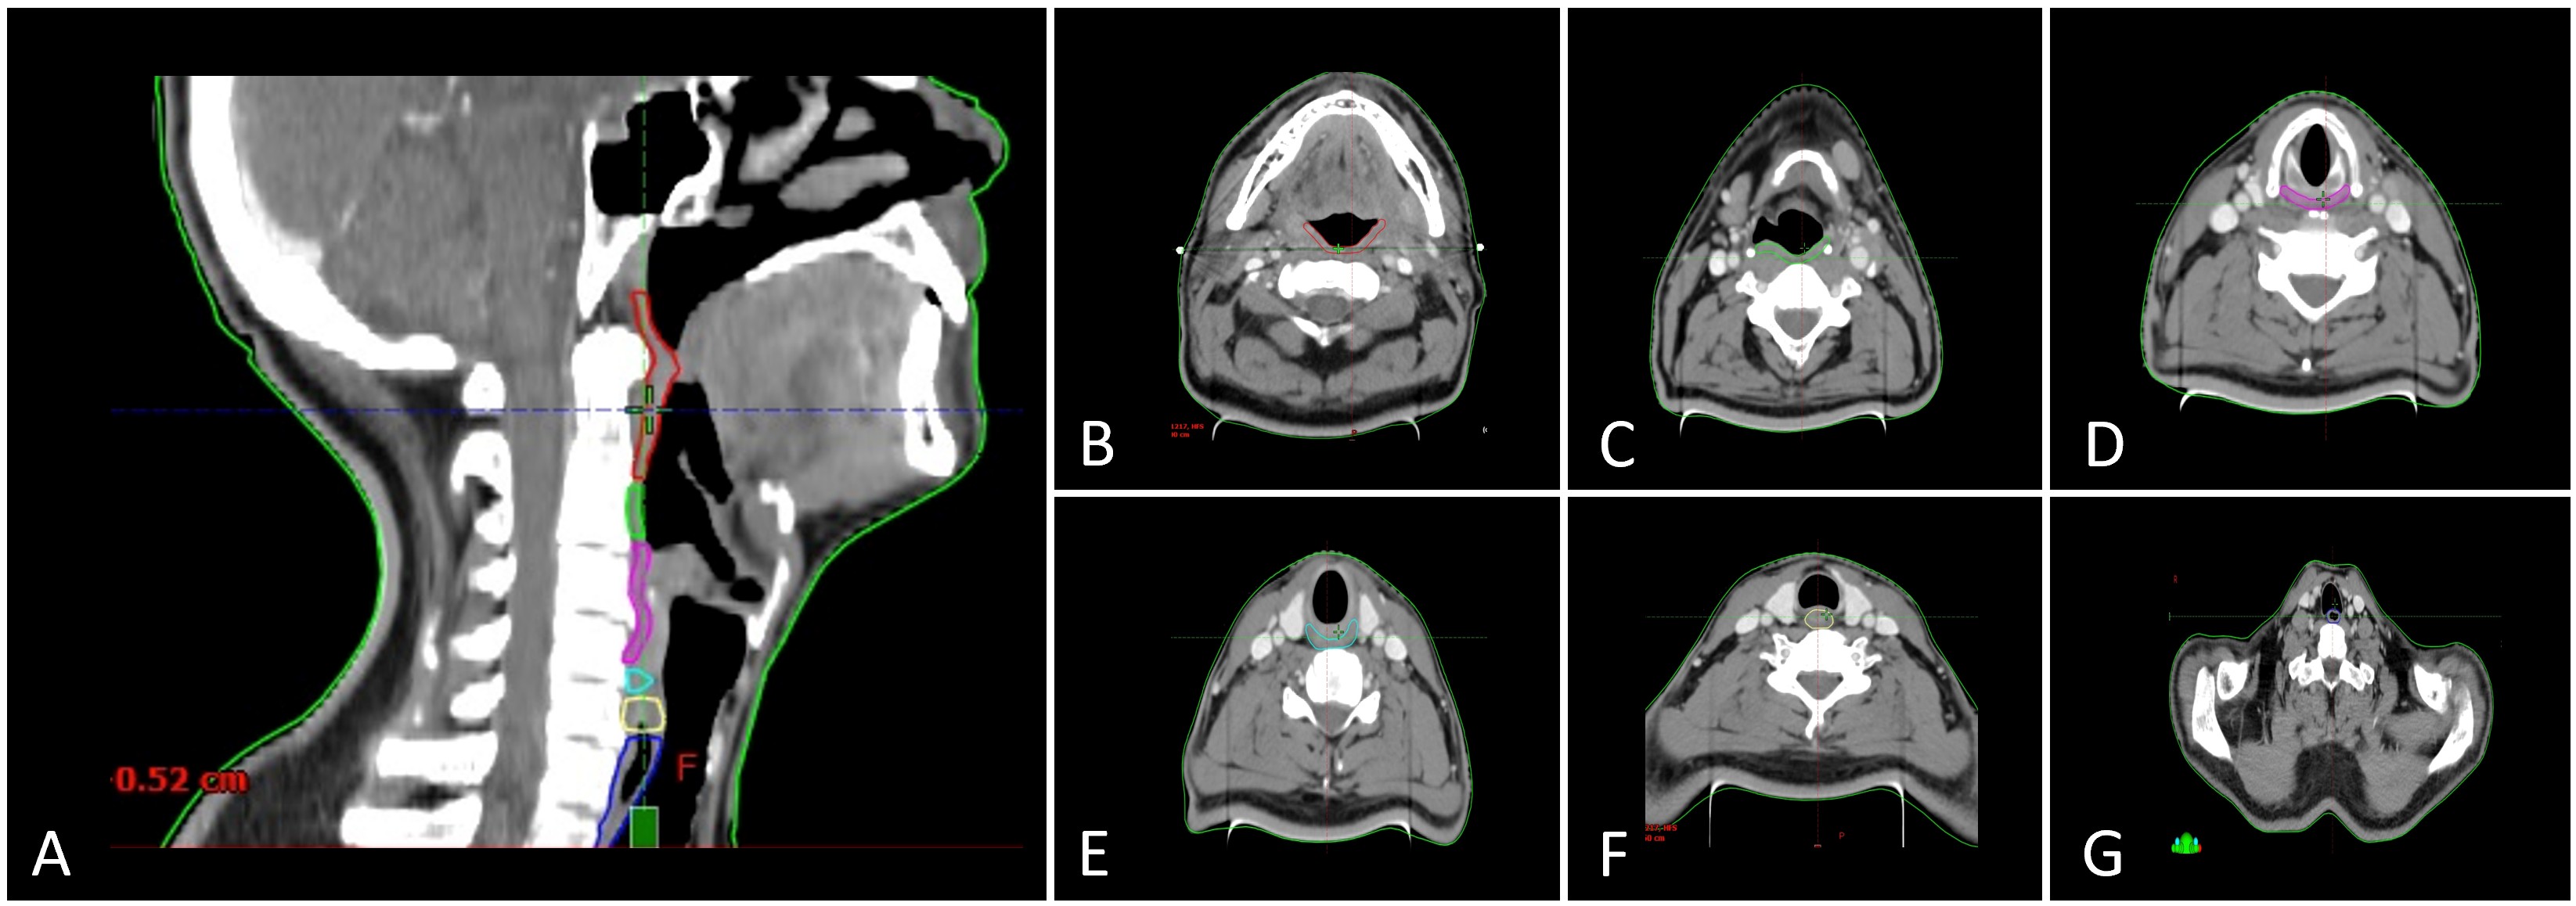

Although more than 30 muscle pairs and six cranial nerves contribute to the intricate coordination of swallowing, not all require contouring for dosimetric analysis. Current consensus highlights a core set of anatomical structures that are most relevant to dysphagia and aspiration, including the pharyngeal constrictors, cricopharyngeus muscle, esophageal inlet musculature, cervical esophagus, and larynx (Table 1, Figure 1) [7].

Figure 1. Anatomical delineation of swallowing-related organs at risk on computed tomography (CT). (A) Sagittal CT section with color-coded contours delineating key swallowing-related organs at risk: superior pharyngeal constrictor (red), middle pharyngeal constrictor (deep green), inferior pharyngeal constrictor (magenta), cricopharyngeus (cyan), esophageal inlet (yellow), and cervical esophagus (deep blue). (B) Axial CT section at the level of the superior pharyngeal constrictor (red). (C) Axial CT section showing the middle pharyngeal constrictor (deep green). (D) Axial CT section depicting the inferior pharyngeal constrictor (magenta). (E) Axial CT section highlighting the cricopharyngeus (cyan). (F) Axial CT section illustrating the esophageal inlet (yellow). (G) Axial CT section of the cervical esophagus (deep blue).